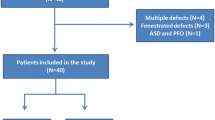

This was a prospective observational study which initially included 64 patients who were referred for elective ASD device closure over a period of 12 months.

Patients with any of the following criteria were excluded from the study: (1) Primum ASD (2) Eisenmenger syndrome (3) associated congenital anomalies requiring surgical intervention (4) Secundum ASD with unsuitable anatomy for closure due to defective or floppy rims diagnosed by transthoracic or transoesophogeal echocardiography (5) Secundum ASD larger than 36 mm in diameter (6) Patients with inter atrial septal aneurysm or fenestrated septum with multiple defects for which 3D tracing of the defect to produce 3D derived area and circumference deemed impossible or inaccurate.

All patients included in the study underwent 2D TTE and TEE, thirty-four patients (68%) were evaluated by 3D TEE and sixteen patients (32%) were evaluated by 3D TTE (Fig. 3). The mean ASD diameter measured by 2D TTE was 15.95 +/- 5.82 mm in sub costal sagittal view, 15.85 +/- 5.99 mm in sub costal biatrial view and 14.58 +/- 7.01 mm in parasternal short axis view, while the mean value for maximum ASD diameter in 2D TEE was 16.74 +/- 6.33 mm. The mean maximum and minimum ASD diameters measured by 3D echocardiogram were 17.7 +/- 6 mm and 14.47 +/- 6 mm respectively.